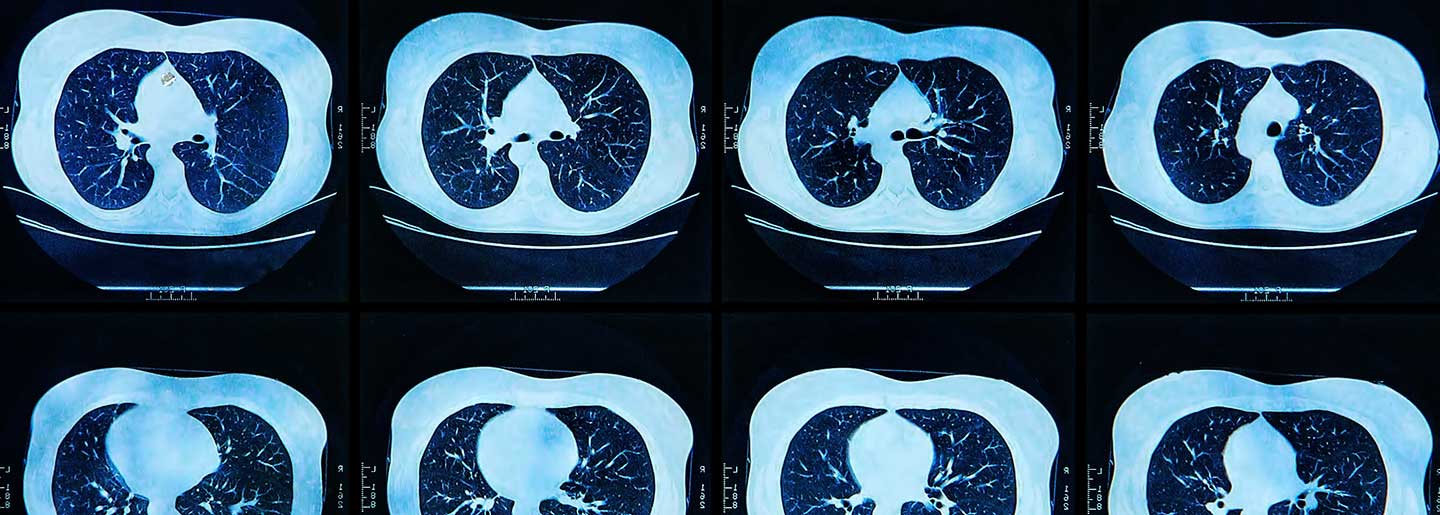

In a new article published in Nature Communications, the research team demonstrates how a deep learning model using positron emission tomography/computerized tomography radiomics can identify which non-small cell lung cancer patients may be sensitive to tyrosine kinase inhibitor treatment and those who would benefit from immune checkpoint inhibitor therapy. The model uses PET/CT imaging with the radiotracer 18F-Fluorodeoxyglucose, a type of sugar molecule. Imaging with 18F-FDG PET/CT can pinpoint sites of abnormal glucose metabolism and help accurately characterize tumors.

For the study, the Moffitt team developed an 18F-FDG PET/CT-based deep learning model using retrospective data from non-small cell lung cancer patients at two institutions in China: Shanghai Pulmonary Hospital and Fourth Hospital of Hebei Medical University. The model classifies EGFR mutation status by generating an EGFR deep learning score for each patient. Once created, the researchers further validated the model using patient data from two additional institutions: Fourth Hospital of Harbin Medical University and Moffitt Cancer Center.